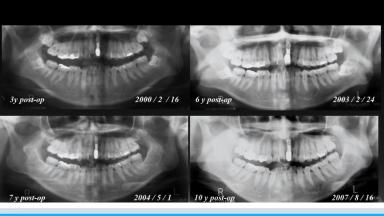

顎骨の成長が終了していない若年者へのインプラント治療は相対的禁忌と考えられている。しかし、患者本人や家族の希望があり、利益が不利益を上回ると考えられる場合には検討を要する。本講演では演者が経験した20年経過の1症例を通して、若年者へのインプラント治療のリスクや治療戦略について解説している。